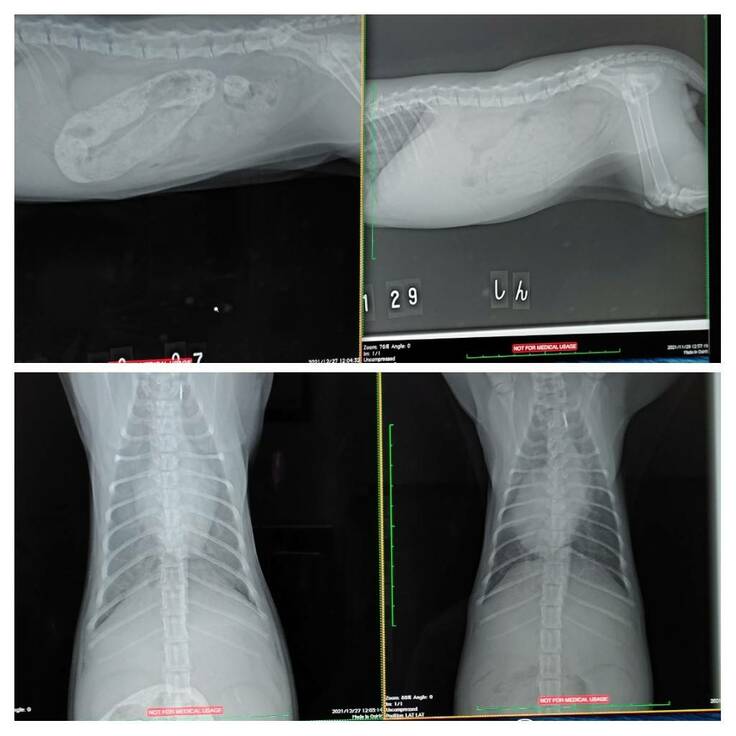

X線写真→左上下が今回、右上下が前回

↑の写真の左上下が今回分のX線写真で、右上下が前回(11月29日)のX線写真になります。

下の左右を比べると、成長しているのも分かりますが、白い影も見えていて、肺の辺りが炎症を起こしているので、これも、"新薬の量が足りてない可能性" があるそうです。

前回、胃が癒着していたっぽいのは、解消された様です。